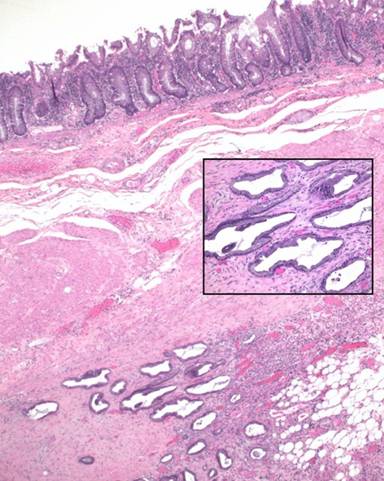

The gross specimen consisted of a partial colectomy with attached distal pancreas and spleen. Gross examination revealed white, ill-defined tumor nodules originating from the tail of the pancreas causing an extrinsic stricture of the colon, but not involving the colonic mucosa itself. Microscopically, the tumor was a pancreatic ductal adenocarcinoma with mucinous differentiation and extension into the wall of the colon where it was limited to the colonic serosa and smooth muscle (Figure 2). The tumor involved the tail of the pancreas and peripancreatic fat (Figure 3). Final staging was T4, N1, Mx, 7/15 lymph nodes were positive for metastasis.

Figure 2. Pancreatic adenocarcinoma involving the colonic wall and subserosal fat with associated acute inflammatory cells secondary to colonic perforation elsewhere. Note that the tumor does not involve the colonic mucosa. (H&E, 20x). Inset: cytoplasmic and intraluminal blue mucin is present consistent with mucinous differentiation (H&E, 100x). |